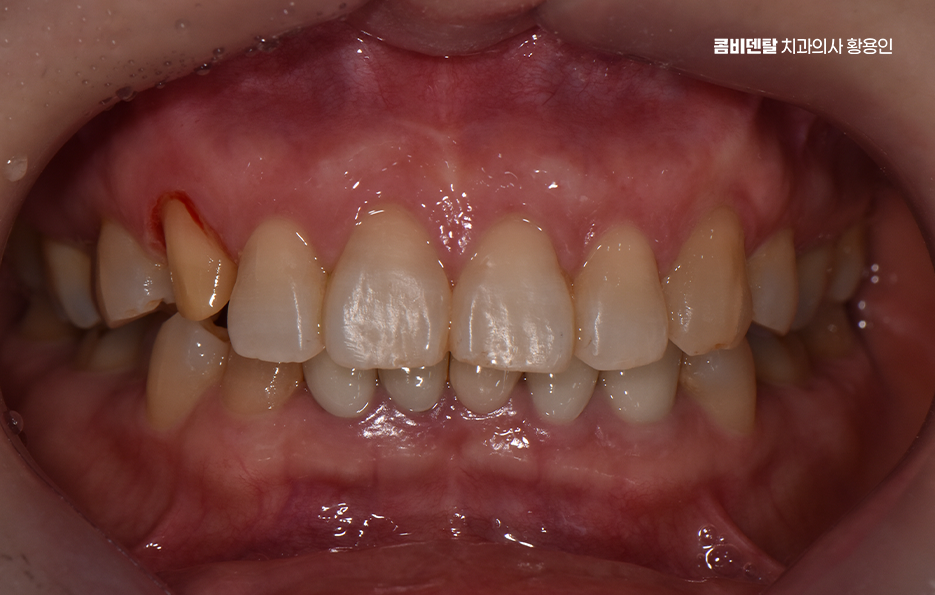

어릴 때는 송곳니가 나름의 포인트처럼 보였고, 웃을 때 조금 튀어나와 보이는 게 오히려 귀여운 느낌이라고 생각했을 만큼 별다른 불만도 없었고, 기능적으로도 별 신경 쓰지 않고 살았는데, 어느 날 그 송곳니에 작은 금이 간 걸 발견하면서부터 생각이 달라지게 됐어요, 처음에는 단순히 스치듯 지나가는 불편함이었고, 거울을 봐도 겉으로는 별다른 이상이 없었기에 그냥 피곤하거나 단단한 걸 씹다 살짝 충격을 받은 것뿐이겠지 하고 넘겼어요, 그런데 시간이 지나면서 그 송곳니 주변에 묘한 감각이 생기기 시작했고, 특히 찬물이나 단 음식이 닿을 때마다 찌릿한 시림이 점점 더 자주 찾아오면서 단순한 문제가 아니라는 걸 실감하게 됐어요. 정확히 언제, 어떤 이유로 그렇게 손상이 된 건지는 알 수 없었지만, 분명한 건 그동안 송곳니가 많은 역할을 해왔다는 거였어요, 다른 치아에 비해 뿌리도 깊고, 입꼬리 쪽에서 중요한 균형을 잡아주는 역할을 하다 보니 교합이나 저작 시에도 무게를 많이 견디는 위치인데, 그만큼 미세한 손상이 쌓이면 결국 파절이나 크랙으로 이어질 수 있다는 걸 나중에야 알게 됐어요, 다만 이미 치질이 약해진 상태라서 송곳니 크라운을 해야 했는데 송곳니는 눈에 잘 띄는 치아 중 하나인데, 거기를 깎고 덮는다는 게 쉽게 받아들여지진 않았고, 뭔가 내 얼굴 전체 인상이 바뀌는 건 아닐까 하는 걱정도 들었어요.

이처럼 송곳니의 손상은 비교적 눈에 잘 띄는 부위에 속하기 때문에 앞니 만큼이나 심미적인 치료가 중요한 부위이기 때문에 크라운 치료를 해야 한다면 심미성과 기능을 함께 고려한 치료가 중요할 수 있는데요

송곳니는 생각보다 입 안에서 중요한 역할을 하는 치아로 기능적으로는 앞니와 어금니를 연결해주는 다리 역할을 하고, 음식물을 자를 때나 씹을 때도 큰 힘을 발휘하는 치아이며 심미적으로도 얼굴 인상에 영향을 주는 위치에 있어서, 문제가 생겼을 때는 치료 방법을 신중하게 선택해야 하는 거예요

송곳니에 크라운 치료가 필요해지는 경우는 보통 충치가 깊게 진행됐거나, 외상으로 깨진 경우, 아니면 이미 신경치료를 한 후에 치아가 약해져서 파절 위험이 있을 때로 송곳니 크라운 치료를 고려할 때 치아의 손상 원인을 잘 분석하여 비슷한 문제가 재발하지 않도록 원인 파악과 개선 또한 무척 중요한데 아무리 치료를 잘 받아도 비슷한 문제가 빠르게 반복된다면 자연치아의 수명도 그만큼 빠르게 줄어들 수 있어요

정리하면 송곳니 크라운 치료를 고민하신다면 사람과 대화하고, 웃고, 감정을 표현할 때 자연스럽게 드러나는 치아이기 때문에 더욱 완성도 높은 치료가 필요하고 치료 자체도 중요하지만 크라운을 씌울 정도로 자연치아의 손상이 이미 발생 했다면 더 추가적인 문제가 진행되지 않도록 꼭 원인 파악과 재발 방지에 힘쓰시길 바라고 있어요